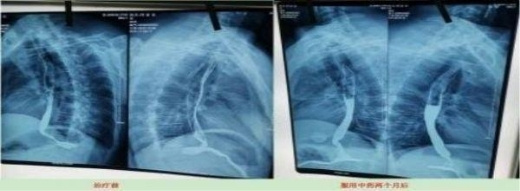

2023年10月9日CT影响报告诊断查出食管壁增厚,管腔狭窄,食管癌。找到陈海林老师使用中医药两个月治疗后CT显示食管各段顺利通过,食管恶性肿瘤治疗后改变。

上图是服用两个月中药的前后对比图

Above is a comparison of before and after taking traditional Chinese medicine for two months

上图是服用两个月中药后检查报告对比图